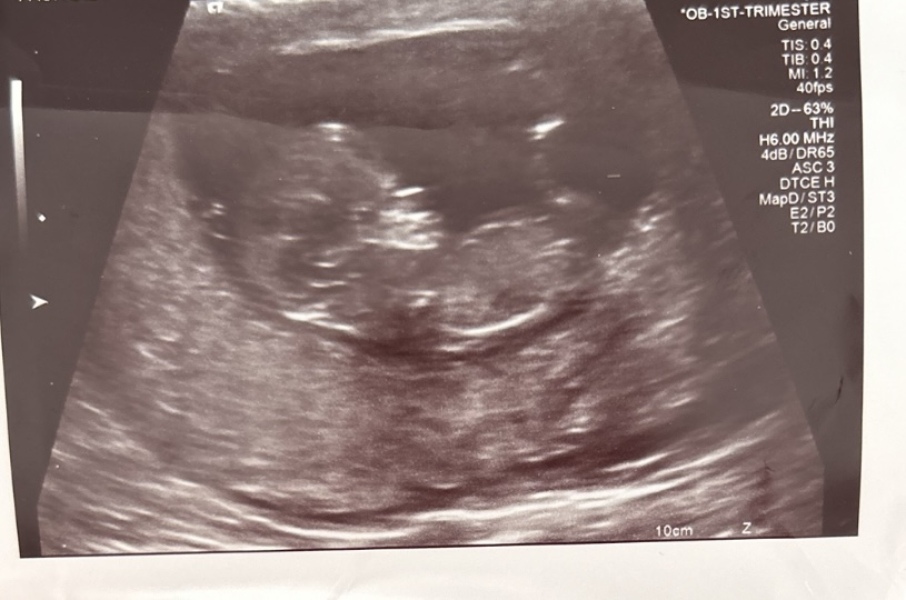

Newtothis5 · 10/02/2017 20:27

Hey all! So when my friends and relatives have been expecting I've loved using 'theories' to guess the gender and quite a lot of the time I have been right. Based on skull and nub theory. We had our scan today and baby is measuring 12 week 5 days. I really wish I had asked for a nub picture as I can't see it on this pic. I think I am swaying more team blue. What do you all think? :)